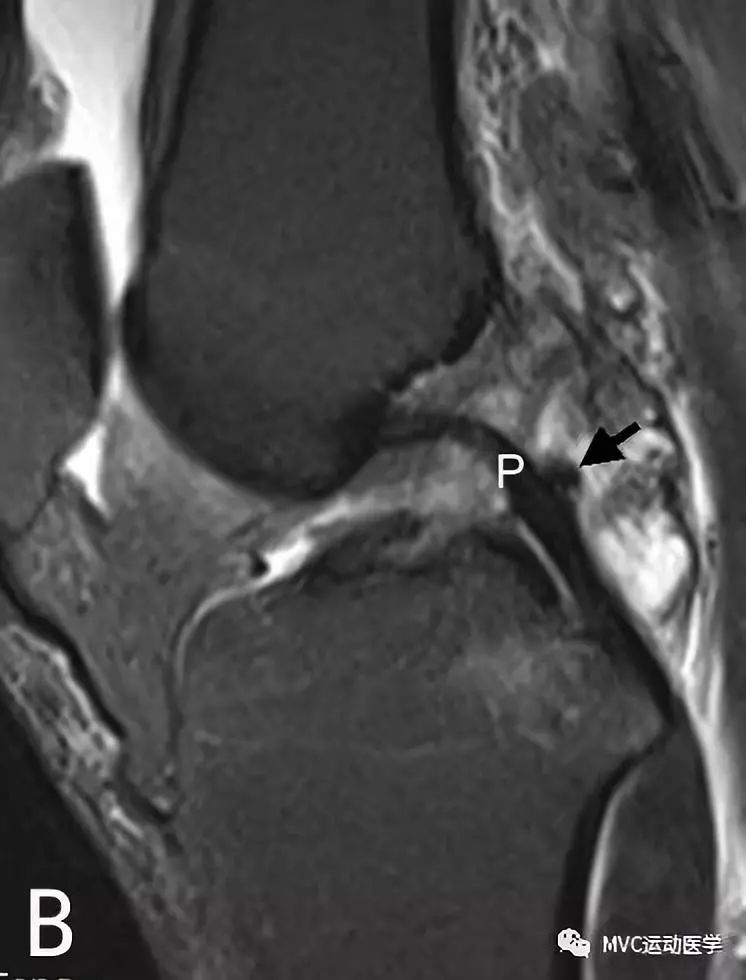

八、半月板股骨韧带

半月板股骨韧带分为两束,两束都起于外侧半月板后角,与PCL并行斜向止于PCL的股骨附着区域。Humphrey束位于PCL前方,PCL后方是Wrisberg束。Wrisberg束较为粗大,直径可达PCL的一半,出现率为74%,Humphrey束出现率为69%,两束同时出现的概率可达50%。在MRI上,Humphrey束出现率为4%,Wrisberg束出现率为80%,可同时观察到双束的仅占1%。Humphrey束在矢状位片上最易观察,也可出现在冠状位上;Wrisberg束在后冠状位上容易观察。

A:冠状位MRI显示外侧半月板后角(白色粗箭头)与Wrisberg韧带(白色细箭头),P代表后交叉韧带

B:矢状位MRI连续扫描,黑色箭头所指为Wrisberg韧带

半月板股骨韧带的半月板附着处易与外侧半月板后角的撕裂相混淆。韧带与半月板之间有液体或脂肪填充,可在MRI表现为由前上至后下的斜行撕裂。当膝关节外旋时,半月板股骨韧带与半月板之间的间隙更加明显,Wrisberg束比Humphrey束更易被误认为是半月板撕裂。